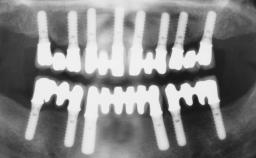

In September of 1995, a 64-year-old female patient presented to our clinic with a distally shortened arch in the left maxilla and the desire for a fixed rehabilitation. The patient’s medical history did not reveal any major issues, and she did not take any significant medication. She was a non-smoker and did not report any allergies.The patient wished to restore her chewing function on the left side, which was severely compromised due to the missing teeth 25, 26, and 27. The antagonistic lower teeth were present and in acceptable condition.